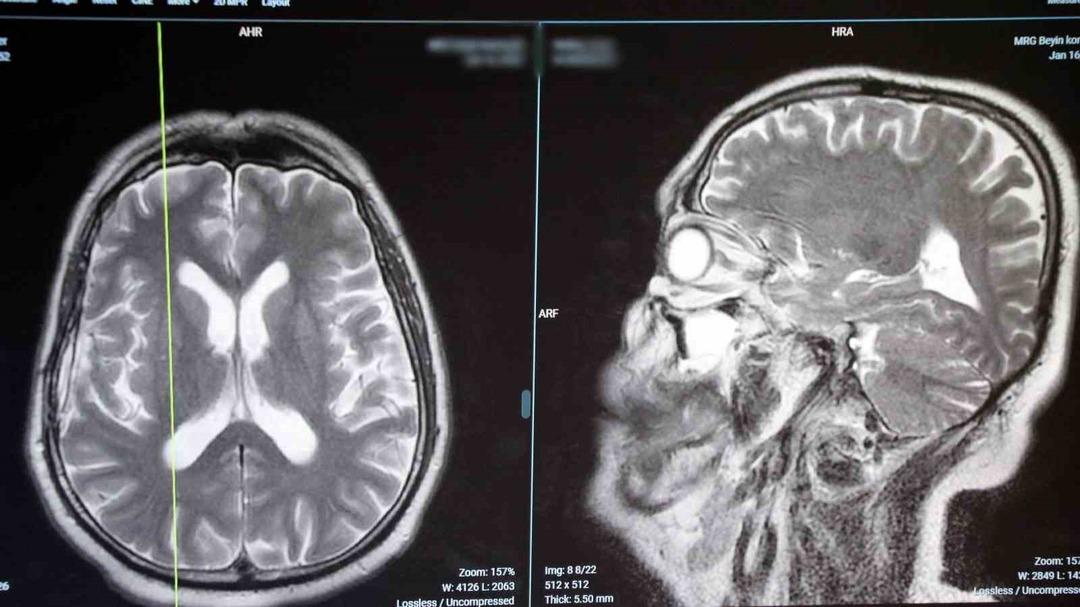

“Koku bozuklukları beyin kanseri, epilepsi ve parkinson gibi hastalıkların bir belirtisi olabilir”

Hastaların en yaygın şikayetleri, Demirel'in kokusu şeklinde yaprak döken meyveler, kokmuş sebzeler, bayat yiyecekler ve tuvalet, “migren saldırısı sırasında nörolojik terimler, koku kokusunu görebilir veya baş ağrısından önce görebileceğimiz baş ağrısından önce. Beynin nöbetini dedim.